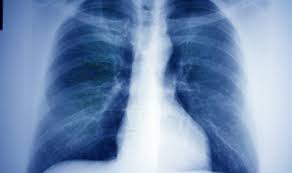

Kreft I Lungene | Lungekreft er ukontrollert celledeling i lungevevet som utvider seg og sprer seg. Lungekreft deles hovedsaklig inn i to typer: Nevroendokrin kreft er en sjelden kreftform som oppstår i hormonproduserende celler som styrer mange av kroppens funksjoner. Lungene er omgitt av en fuktig dobbel hinne, kalt brysthinnen (pleura). I tillegg kan det være spredning av kreft i lungene fra andre steder i kroppen, såkallte dattersvulter/metastaser.

Mange andre organer gir ofte metastase til lungene. Desse er oftast karsinomar med opphav i epitelceller. Lungekreft er kreft som oppstår i lungene eller i luftveiene. Cellene begynner å dele seg og vokse uten hemning. De fleste av dem som blir rammet av lungekreft, er mellom 50 og 70 år. Luftveiene og lungene tilfører kroppen oksygen og fjerner karbondioksyd, et avfallsprodukt fra kroppens energiomsetning. Disse cellene finnes overalt i kroppen. Lungekreft kan spre seg til lymfeknutene, leveren, beina.

For fem år siden holdt lena ronge (57) på å dø av en blodpropp i lungene, etter en kreftoperasjon, selv om hun nå er. Disse cellene finnes overalt i kroppen. Svulsten fremkommer når noen celler i lungene mister selvkontroll. 87 pasienter fikk denne diagnosen i norge i 2017. Flere mekanismer som oppstår ved langtkommet kreft vil også virke ved lungekreft. Mange andre organer gir ofte metastase til lungene. Kreft som oppstår i lungene blir kalla primær lungekreft. Kreft i lungene anses som en alvorlig sykdom fordi den utvikler seg raskt og ofte er fremskreden når den oppdages.

Med lungekreft menes ondartede svulster som oppstår i lungene og / eller luftveiene (bronkiene). Svulsten fremkommer når noen celler i lungene mister selvkontroll. Disse cellene finnes overalt i kroppen. Legene tror at sveden har spist en ert, men at det på mysterisk vis har klart å komme ned feil vei og begynte å gro i lungene. Lungene er omgitt av en fuktig dobbel hinne, kalt brysthinnen (pleura).